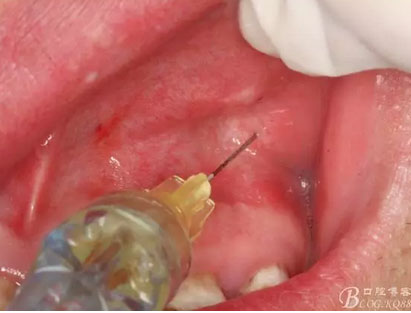

圖5.唇側(cè)局部無痛浸潤麻醉

圖6.腭側(cè)無痛浸潤麻醉:腭乳頭發(fā)白。